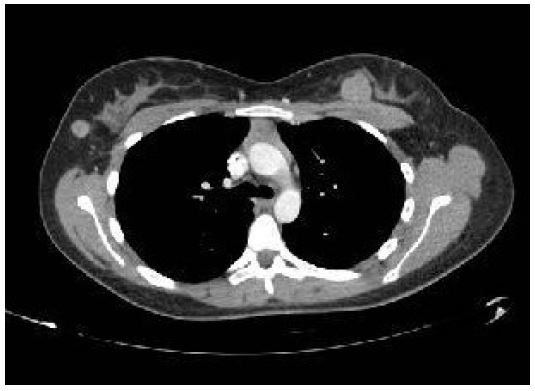

In September 2022, a CT scan of the thorax, abdomen, and pelvis was performed for re-staging. While no pulmonary disease was detected, the scan revealed four suspicious breast nodules (two on each side), as shown in Figure 4. A biopsy later confirmed these nodules to be metastatic sarcoma, identical to the forearm mass, with pathology slides presented in Figures 5 and 6. Prior to the mastectomy, the patient received six rounds of VIT chemotherapy, which included vincristine, irinotecan, and temozolomide. Subsequently, a bilateral mastectomy with partial excision of the pectoralis major muscle was performed in March 2023. The procedure was successful, and no complications were reported. The patient was subsequently referred to physiotherapy.

Figure 4: Axial CT scan revealing bilateral breast metastatic deposits.